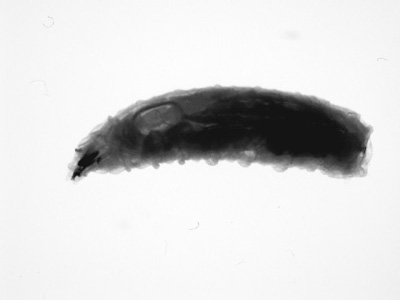

DPDx is an educational resource designed for health professionals and laboratory scientists. For an overview including prevention, control, and treatment visit www.cdc.gov/parasites/.